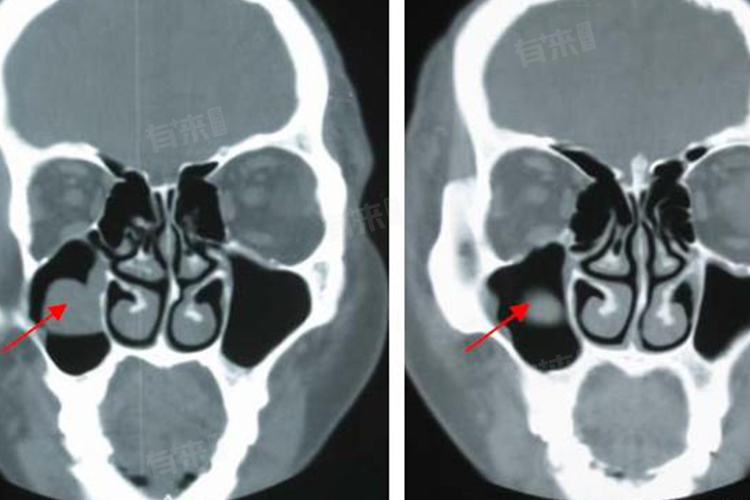

3、诊断:上颌窦黏膜下囊肿的诊断主要依赖于影像学检查,如鼻窦CT或MRI,这些检查能够清晰显示囊肿的位置、大小、形态以及与周围组织的关系,为临床诊断提供重要依据,结合患者的症状、体征及病史,可作出综合判断。